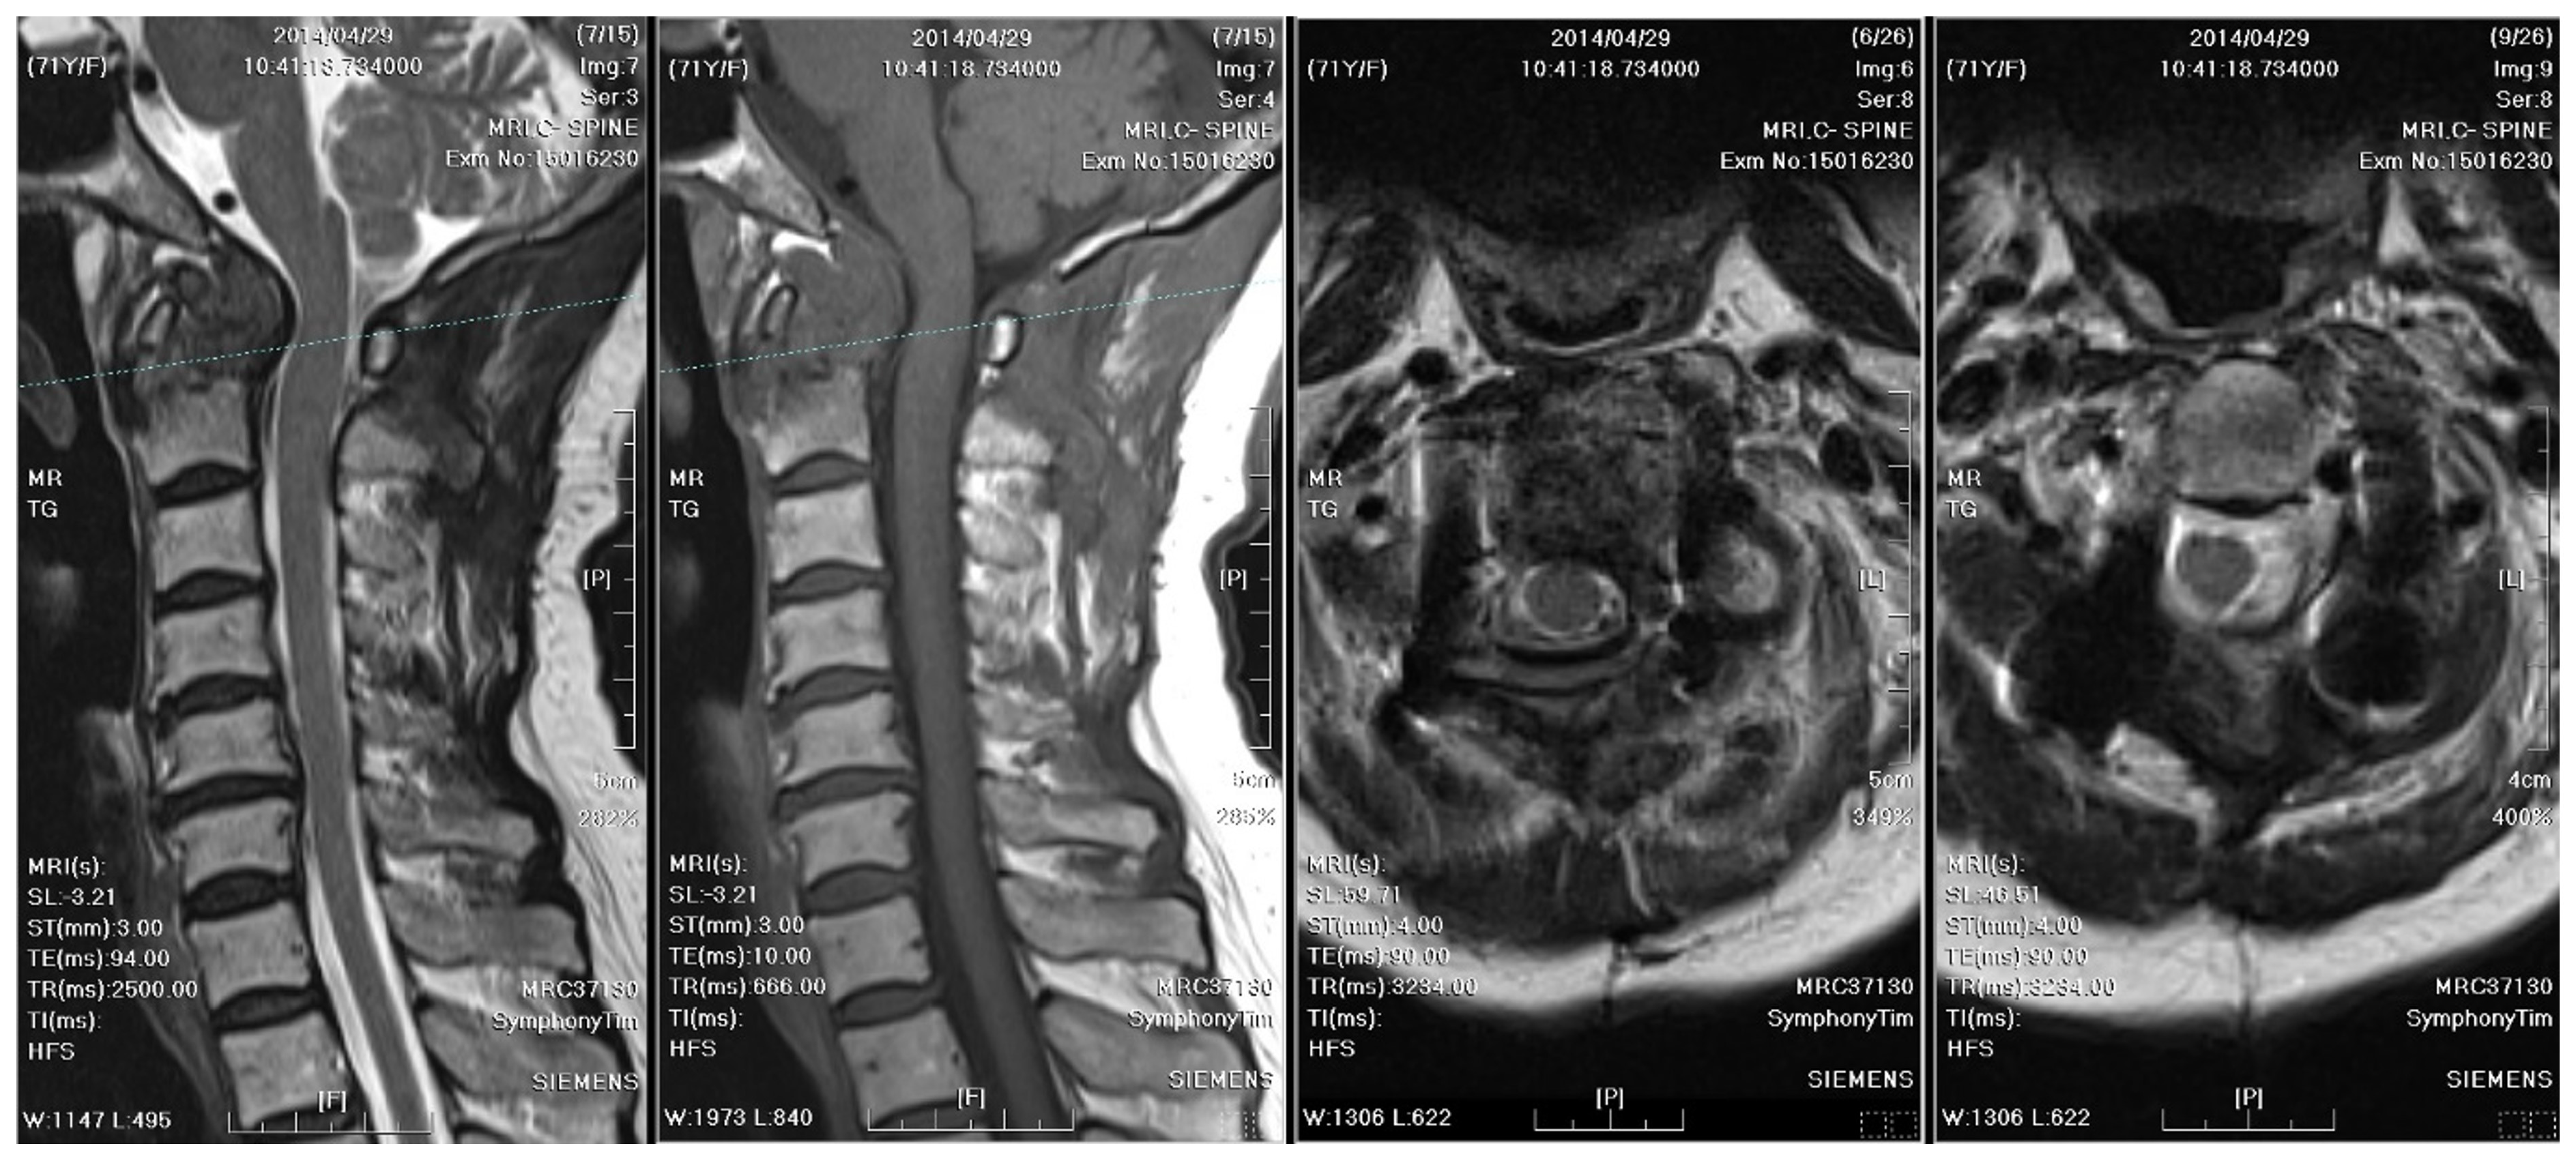

Emergent decompressive surgery was performed via a transoral approach, revealing cheese-like pus and caseous necrotic tissue, with the pathologic examination showing chronic inflammatory tissue, necrosis, and dystrophic calcification. In addition, the transoral approach facilitated prompt abscess evacuation and prevention of unnecessary damage to the nearby vital neurovascular structures. The AFB smear and culture of the specimen confirmed TB spondylitis (Figure 6). However, the sputum culture and chest radiograph did not reveal concurrent pulmonary TB. Based on local guidelines for TB treatment in Taiwan [10], a 12-month antitubercular regimen was adopted. The treatment started with ethambutol/rifampin/pyrazinamide/isoniazid for three months, then shifted to rifampicin/isoniazid for nine months. During regular follow-up visits at the neurosurgery outpatient department every three months, significant neurological improvement was observed. A substantial reduction in the size of the mass, rendering it nearly undetectable, was observed on subsequent annual MRI scans (Figure 7).

Figure 7. MRI and radiographs of cervical spine after antitubercular treatment: A 12-month antitubercular treatment regimen led to significant neurological improvement and a substantial reduction in the size of the mass, which became nearly undetectable on subsequent MRI. The stabilization remained fair.